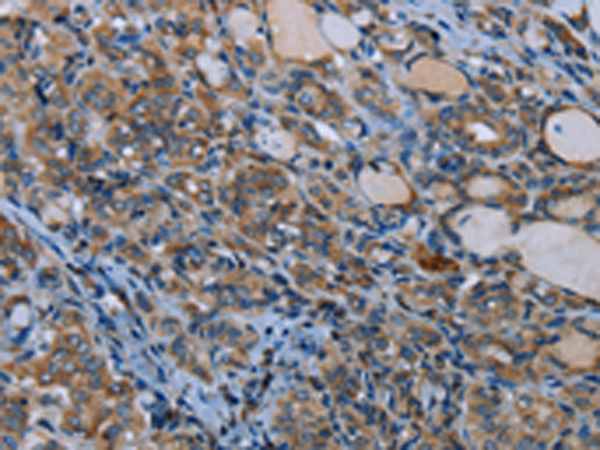

分类: 科研抗体货号: P08427别名: IDH; IDP; IDHM; IDPM; ICD-M; D2HGA2; mNADP-IDH应用: WB,IHC反应种属: Human, Mouse, Rat